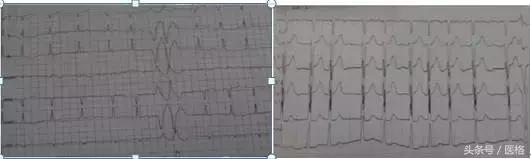

②心电图检查:房颤心律,偶发房性早搏(图1);

图1:房颤心律,偶发房性早搏